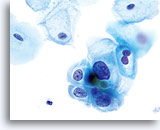

En raison de leur morphologie, les cellules issues de lésions de bas grade comptent parmi les anomalies intra-épithéliales les plus faciles à localiser et à identifier. En comparaison, les noyaux LSIL sont les plus grands et présentent un rapport N/C inférieur aux HSIL ou carcinomes. Ces cellules affichent une atypie nucléaire plus importante que les ASCUS (ce qui se traduit par une augmentation de la taille nucléaire, une irrégularité de la chromatine et une irrégularité de l’enveloppe nucléaire). Les noyaux peuvent occasionnellement ne pas être aussi hyperchromatiques que sur les frottis conventionnels, mais ils le sont toujours par rapport aux cellules normales environnantes. Les changements associés au HPV (par exemple, formation de cavités dans le cytoplasme) sont plus évidents grâce à la fixation liquide et à la technique de transfert, ce qui élimine la déformation des cellules associée à la méthode d’étalement conventionnelle. La méthode ThinPrep préserve mieux ces changements cellulaires, ce qui permet une meilleure distinction entre les véritables cavités cytoplasmiques induites par le HPV et les vacuoles bénignes/dégénératives et/ou les cellules malpighiennes glycogénées.

Comme il s’agit de cellules malpighiennes matures, elles gardent leur forme polygonale et conservent en partie leur taille normale. La taille des noyaux est au moins 3 à 4 fois supérieure à celle d’une cellule intermédiaire normale. En revanche, quand les changements associés au HPV sont évidents, les cellules peuvent être plus petites (quasiment parakératosiques), tout comme les noyaux (quelque peu pycnotiques) qui présentent en outre une binucléation et/ou multinucléation. Ces noyaux pycnotiques affichent en outre des caractéristiques anormales : hyperchromasie, augmentation de la taille par rapport à une cellule malpighienne superficielle normale, légère variation de la forme et de la taille, etc. Il est important d’insister sur le fait qu’une interprétation de LSIL/HPV implique des cavités cytoplasmiques nettes accompagnées de la morphologie nucléaire anormale décrite ci-dessus.